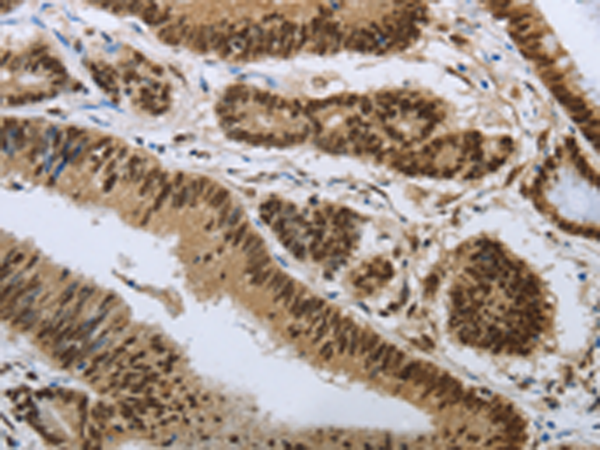

分类: 科研抗体货号: P11096别名: HRMT1L3应用: IHC反应种属: Human